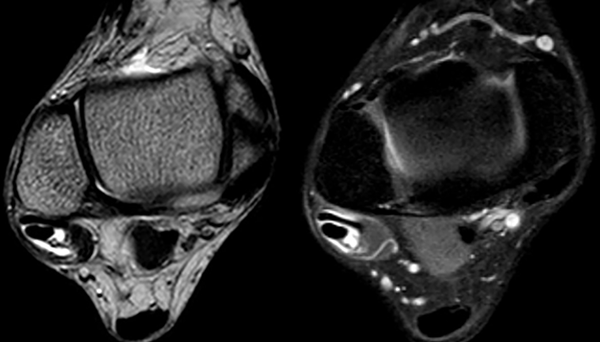

La RM es el método estándar para evaluar patologías de los tendones.31 Los cortes axiales con el pie en 20° de flexión plantar muestran las mejores imágenes anatómicas de los TP, el contenido de la vaina sinovial y las estructuras vecinas, el RPS y la escotadura retromaleolar.27,28 En los cortes sagitales se evalúa la longitud de la patología.28 Los TP sanos presentan una intensidad baja y homogénea en T1 y T2, así como en las imágenes STIR. En TP dañados se puede encontrar una heterogeneidad e intensidad de señal aumentada en todas las imágenes.20,28

La tenosinovitis se puede reconocer con una sensibilidad del 17% y una especificidad del 100% cuando hay más de 3 mm de diámetro de líquido dentro de la vaina sinovial (fig. 5).29

Figura 5: Los cortes axiales de resonancia magnética a nivel de tobillo en leve flexión plantar son los que mejor definen la anatomía de los tendones peroneos. En la imagen T1 y T2 muestran más de 3 mm de líquido dentro de la vaina sinovial.

La especificidad de la RM para detectar roturas del TPB se ha informado en un 80%, un 100% para detectar roturas del TPL y un 60% para roturas de ambos. En las imágenes de T2, las roturas agudas tienen una alta intensidad de señal y pueden parecer en forma de “C”, bisectadas o aplanadas.29 Sin embargo, tiene menos utilidad para diagnosticar variaciones anatómicas, como un VMPBB o un MPQ.32 La RM también puede revelar lesiones del RPS.